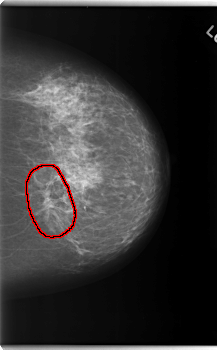

FILE: C_0173_1.LEFT_MLO.OVERLAY TOTAL_ABNORMALITIES 1 ABNORMALITY 1 LESION_TYPE MASS SHAPE IRREGULAR MARGINS ILL_DEFINED ASSESSMENT 5 SUBTLETY 5 PATHOLOGY MALIGNANT TOTAL_OUTLINES 1 BOUNDARY |